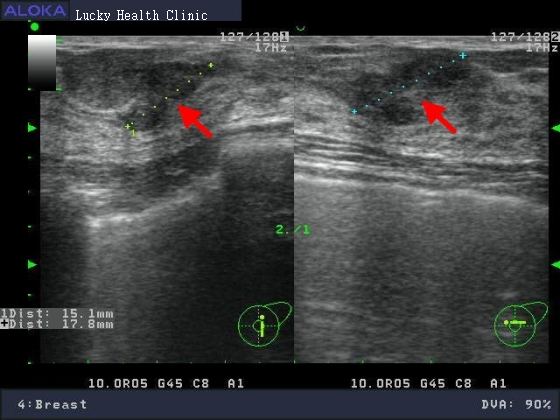

醫學影像..乳房超音波

分類 3:可能良性發現,惡性度< 2%(建議短期間追蹤)